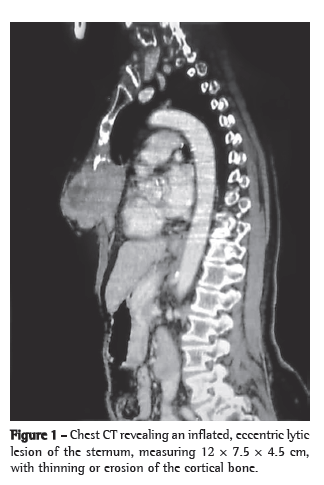

A 74-year-old White female homemaker sought medical attention. The patient reported having been initially examined at another facility due to a fall from standing height. At the time, the tests revealed a tumor of the sternum. She presented with constant localized pain (without irradiation) that was partially controlled with analgesics. The patient stated that she used hydrochlorothiazide (25 mg/day) for the treatment of systemic arterial hypertension. She reported no recent respiratory infection or previous contacts, nor did she report a personal or family history of cancer. She described herself as a nonsmoker. Physical examination revealed that she was in good general health, with good color, and well as being well hydrated, stable and without changes in the other systems. She had a fixed, fibroelastic tumor, which was painful on palpation, affecting nearly two thirds of the sternum. There was no local phlogosis or evidence of incisional biopsy scarring. The patient provided the result of a pathological examination performed at another facility, the findings of which were suggestive of a brown tumor, which is a type of GCT. At the outpatient clinic of the Cancer Hospital of Barretos, complementary tests (chest CT and biochemical profile) were requested. The biochemical test results (serum levels of phosphorus, parathyroid hormone, and calcium) were normal. A CT scan of the chest revealed a lytic process (12 × 7.5 × 4.5 cm) affecting the cortical layer of the sternum, as well as a nonspecific pulmonary nodule (8 mm) in the lower lobe of the left lung (Figure 1). The patient underwent surgical resection of the tumor with full-plane oncologic margins (monobloc resection), followed by pulmonary nodule resection and chest wall reconstruction with fascia lata. The surgical specimen showed a bone tumor containing lacunae and scattered areas of hemorrhaging. Macroscopically, the surgical margins were free of disease (Figure 2). The postoperative evolution was favorable, and the patient was discharged on day 6. Definitive pathological examination confirmed GCT, with disease-free margins, and the pulmonary nodule had a necrotic aspect. Outpatient follow-up evaluation revealed that the pain experienced by the patient decreased and there was no disease recurrence as of the fifth postoperative month.

There have been only a few isolated reports of GCTs affecting the axial skeleton. Although typically benign (malignancy rate, 2-8%), GCTs are locally aggressive.(3,4) In most cases, GCTs occur between the third and fourth decades of life, cases such as the one reported here (occurring in the seventh decade of life) being quite rare.(1) In 81% of the cases, GCTs affect Whites.(1) The major clinical manifestation is intermittent, localized pain, with or without swelling in the affected region.(1) The duration of the illness varies.(4) Some patients seek treatment because of the pain, others seek treatment because of their perception of the tumor or because of pathological fracture, associating the symptom onset with a particular trauma.(1) As shown in the present report, the classical radiological features of GCTs define them as eccentric lytic lesions, with thinning or erosion of the cortical bone.(1) In general, a single bone is affected.(3,5-8) The clinical, radiological, and histological characteristics of GCTs are similar to those of tumors and pseudotumors such as brown tumors of hyperparathyroidism, aneurysmal bone cysts, epiphyseal chondroblastomas, osteoblastomas, and non-osteogenic fibromas.(1) A working diagnosis of brown tumor (associated with hyperparathyroidism) can be confirmed by biochemical changes in serum levels of calcium and phosphorus.(1) In this report, biochemical tests that helped narrow down the list of possible differential diagnoses were requested, obviating the need for other tests. Magnetic resonance imaging is indicated to define the limits of the tumor and its characteristics as a homogeneous solid lesion, which might present areas containing liquid, resulting from tumor necrosis or from mingling with an aneurysmal bone cyst.(3,5-8) On bone scintigraphy images, an area of intense uptake indicates an increase in reactive osteoblastic activity and allows the investigation of other foci.(3) Due to its high cost and the prioritization of patients, this test was not performed in this case. Chest CT, perhaps aided by the anatomical location of the lesion, proved to be sufficient to clarify the lesion characteristics and limits, providing an overall assessment of the pulmonary nodule. Histologically, GCTs consist of giant cells interposed with spiral and ovoid cells (Figure 3).(3) Some authors, in attempts to determine a prognosis, classify GCTs by assigning grades to their different forms, taking in consideration the characteristics of the stroma and the number of giant cells present.(1) The quantity of stroma cells in itself does not indicate whether a tumor is benign or malignant.(1) Some studies call attention to the possible association between chromosomal changes (arm 19q) and the occurrence of GCTs.(7) The behavior of GCTs is unpredictable.(1) There have been reports of malignant transformation of GCTs after radiotherapy.(1) Surgical treatment is the only way to achieve a cure and should therefore be used whenever possible.(3,5-8) The follow-up evaluation of patients submitted to surgery in order to excise a GCT should include radiological imaging of the surgical site and of the lungs.(1)